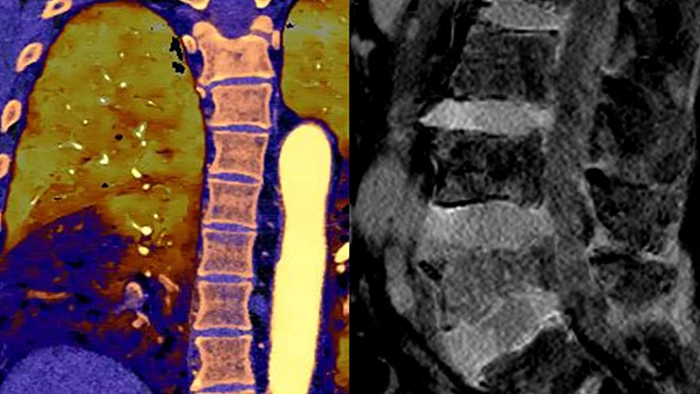

With detector-based spectral, you acquire multiple layers of data—conventional and spectral—within a single exposure and without special scan modes for improved tissue characterization and visualization.

Can you solve the mystery diagnosis using spectral?

Go beyond conventional CT. See how layers of spectral-detector results can enhance your diagnostic confidence.

- Toggle view

Neck mass

See the difference between spectral-detector CT and conventional CT